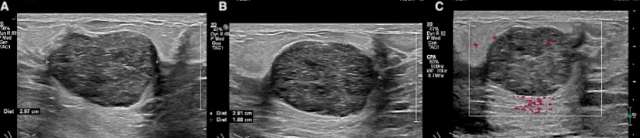

On ultrasound, fibroadenomas are usually well-circumscribed solid or oval masses that are homogenously isoechoic or hypoechoic.1 Fibroadenomas are often hypovascular and small, measuring less than 3 cm.5 Transmission characteristics are nonspecific as fibroadenomas can demonstrate either posterior acoustic enhancement or shadowing.1 As previously described, calcifications may be present. Occasionally, fibroadenomas may have non-circumscribed margins or show interval growth. In such cases, tissue sampling may be warranted to ensure diagnosis.6